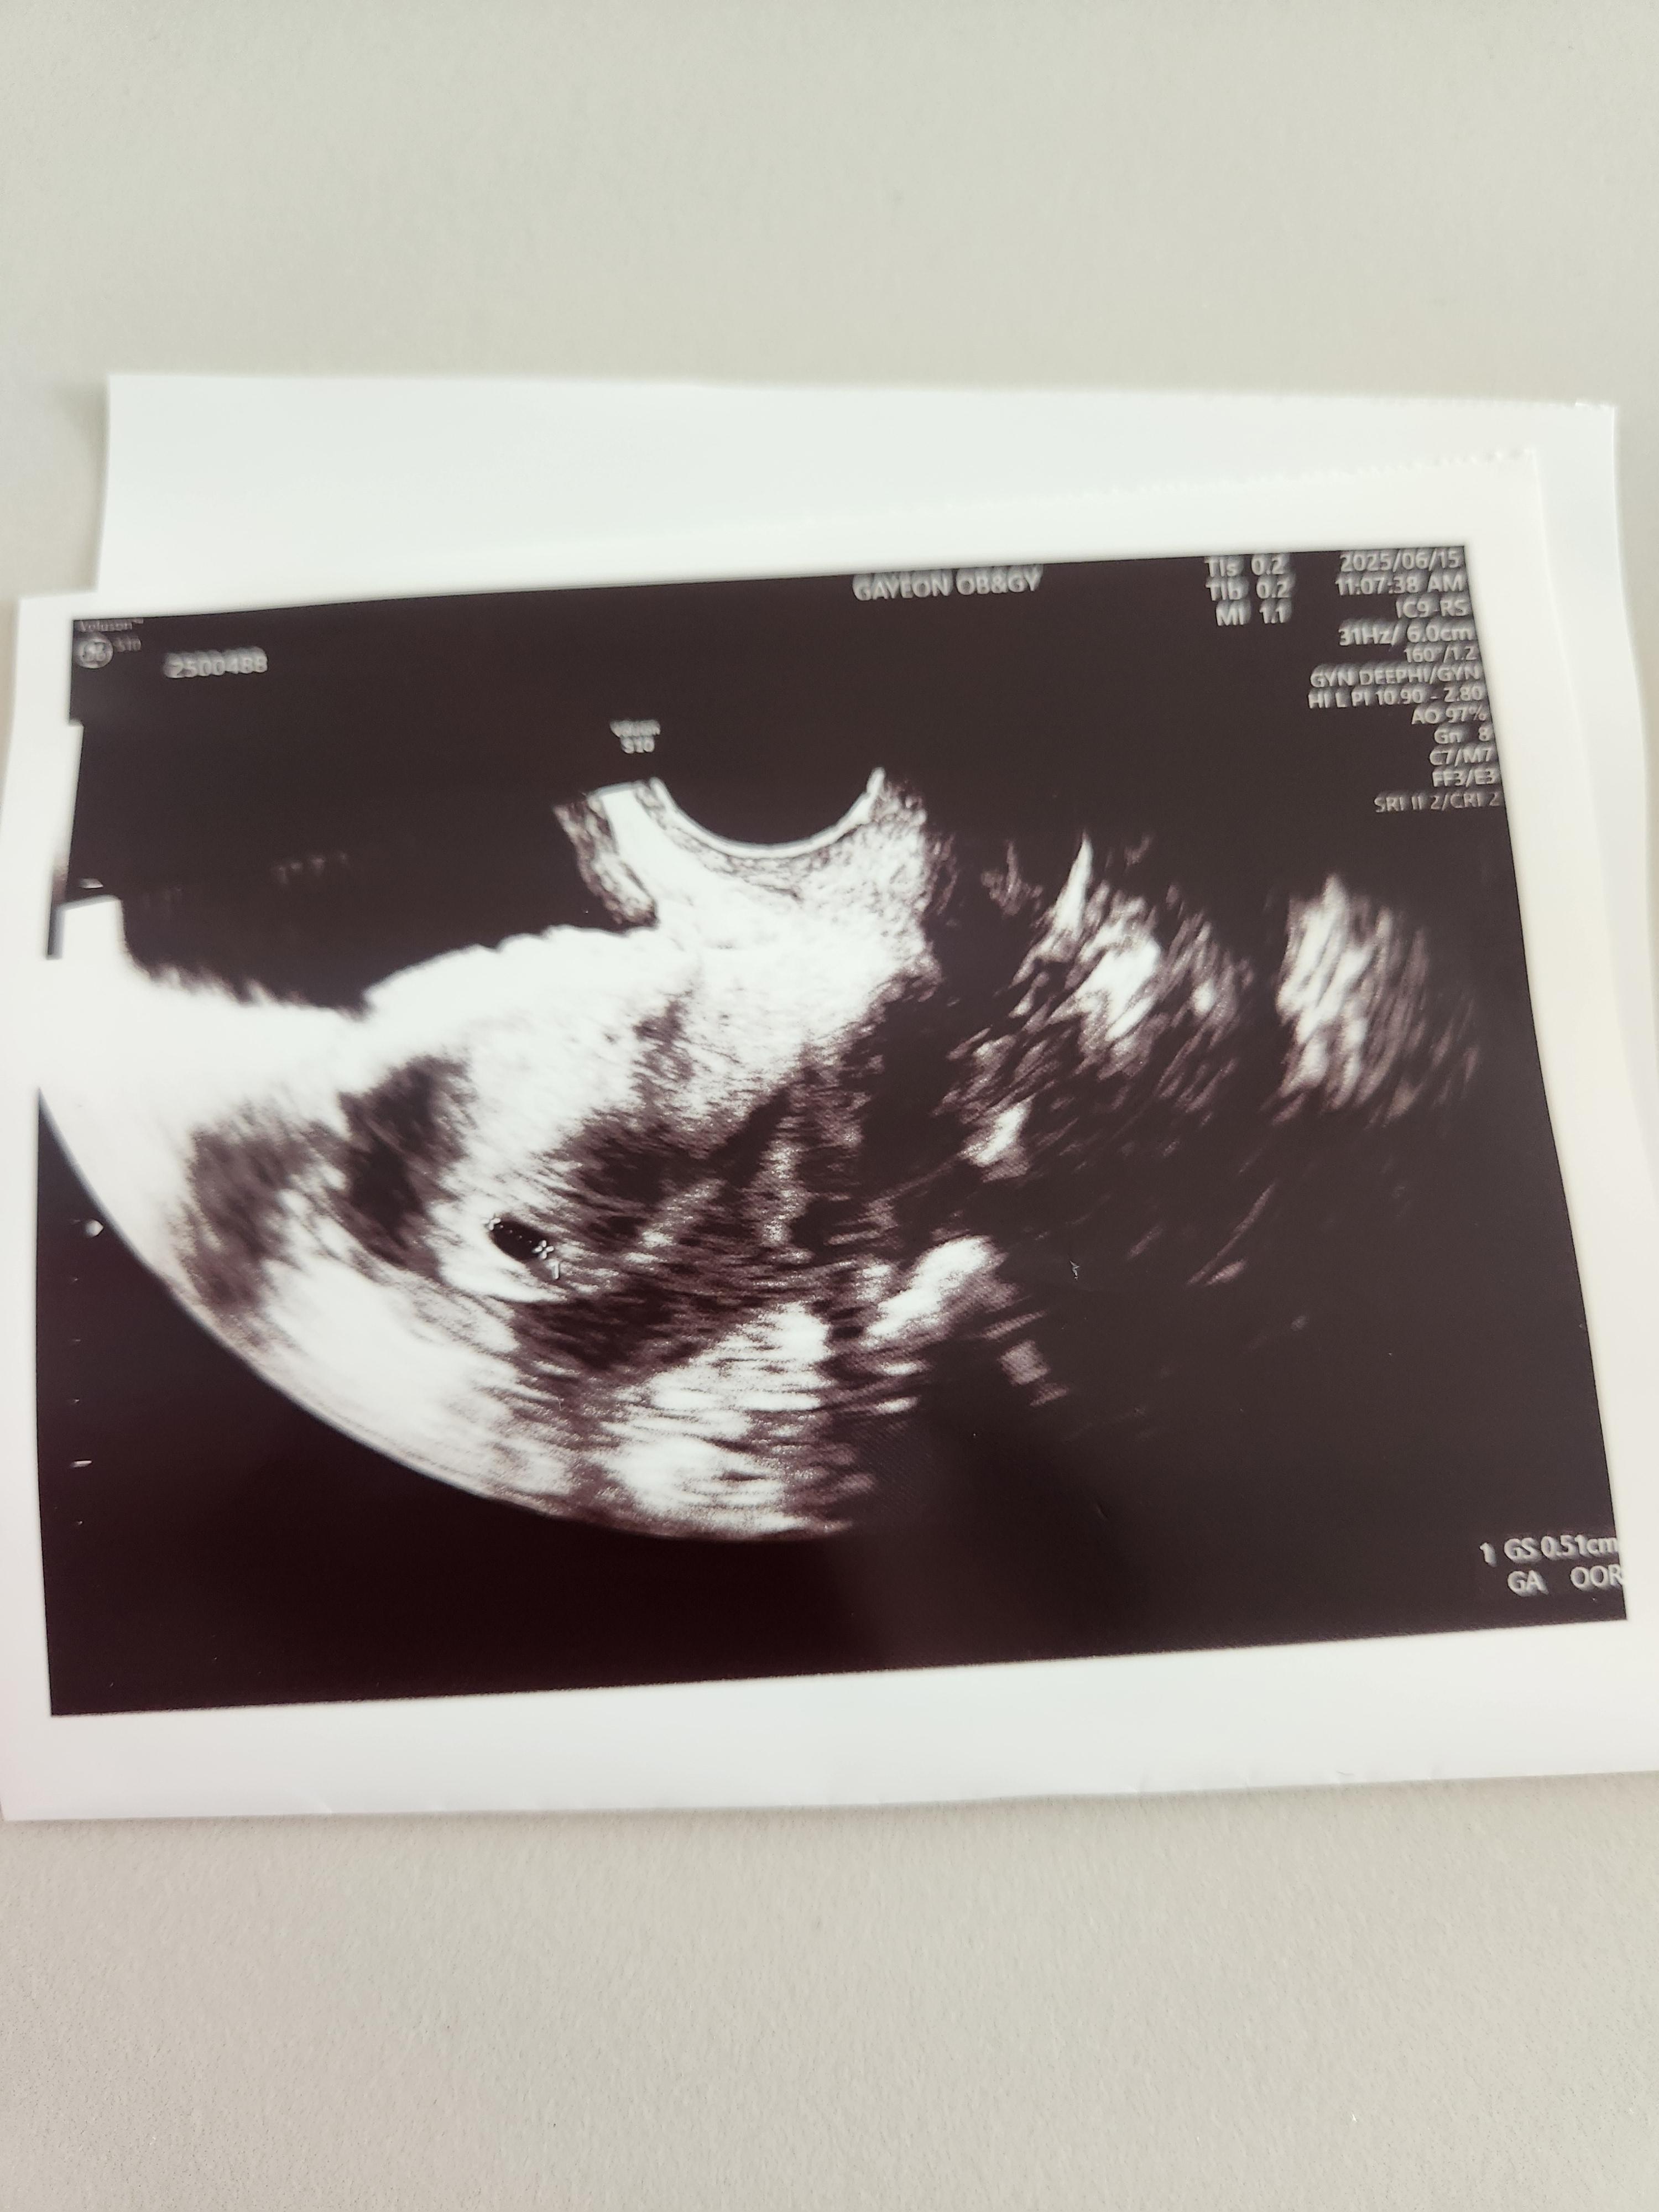

초음파는 질 초음파로 봤고, 아기집을 조그마하게 확인할 수 있었습니다.

아직은 심장소리를 들을 수는 없었고, 주수가 얼마 안돼서 아기집만 볼 수 있었습니다.

일주일 사이에 아기집을 잘 지어놨고, 피고임이나 다른 이상한 것도 없다고 말씀해 주셨습니다.